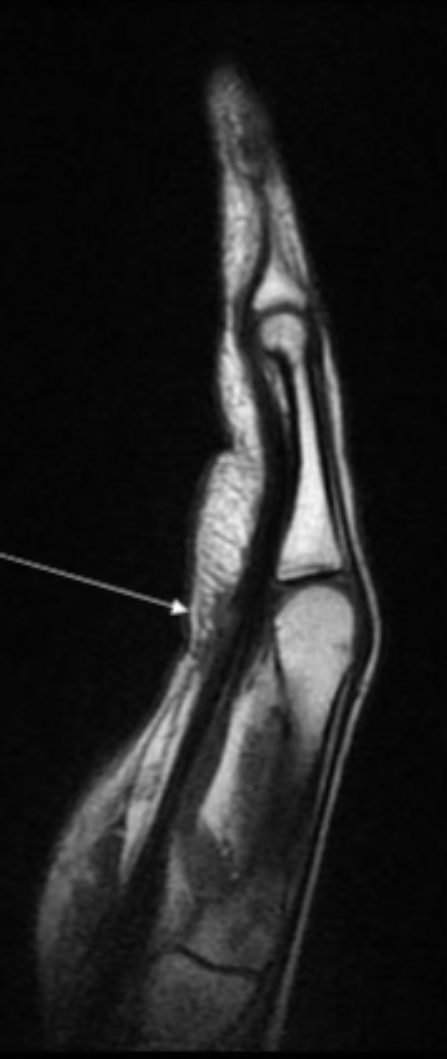

Describe the pathology indicated by the arrow (Sag PD).

Flexor tendon tear